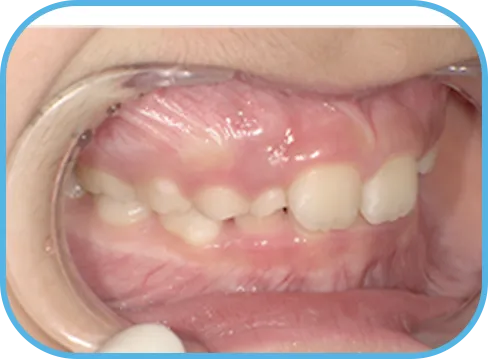

• 右 側

治療前右側からの歯の様子

治療後右側からの歯の様子

• 左 側

治療後左側からの歯の様子

主 訴

前歯が開いている

治療内容

インビザライン・ファースト

治療期間

6か月

治療費(税別)

450,000円+診断料30,000円

リスク・副作用

• 親知らずの影響や加齢などによって、凸凹が生じる可能性があります。

• 治療の初期段階では痛みや不快感が生じやすくなりますが、1週間前後で慣れます。

• 顎の成長発育によって、噛み合わせや歯並びが変化する可能性があります。

• 状況により当初予定した治療計画を変更する可能性があります。